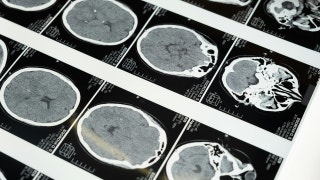

Former Trump economic advisor Steve Moore joins 'Fox & Friends' to discuss the 'historic' White House meeting with AI leaders and how 'energy independence' is fueling both the tech revolution and U.S. military operations. Last summer, a man’s brother-in-law suffered a fatal heart attack. The hospital bill for four hours of emergency care: $195,628. The man’s sister-in-law was ready to pay it. He asked her to wait. He requested an itemized bill with CPT codes (the universal billing codes hospitals use) and fed the whole thing into Claude, an AI chatbot. Within minutes, Claude found duplicate charges, services billed as "inpatient" even though the patient was never admitted, supply costs inflated 500% to 2,300% above Medicare rates and charges for procedures that never happened. He cross-checked with ChatGPT. Both AIs agreed. He wrote a six-page letter citing every violation by name. The hospital dropped the bill to $33,000. An 83% reduction. Zero medical training. A $20 app. A man cross-checked a hospital bill with AI and got it reduced by some 83%. (Neil Godwin/Getty Images) That story sounds extreme. It’s not. The Medical Billing Advocates of America estimates 3 out of 4 medical bills contain errors. The average hospital bill over $10,000 has roughly $1,300 in mistakes. And less than 1% of denied insurance claims are ever appealed. Hospitals and insurers are banking on the fact that you won’t check. AI flips that equation. You don’t need to understand CPT codes or have a medical billing degree. You just need to paste. You can use AI platforms, like ChatGPT, to spot errors or suspicious charges on medical bills. (Jaap Arriens/NurPhoto via Getty Images) Step 1: Call your provider and request an itemized bill with CPT codes. Not the summary. The full line-by-line breakdown. You’re legally entitled to this. Step 2: Open ChatGPT, Claude, Grok or Gemini (free versions work) and paste this: "I’m pasting my itemized medical bill below. Please: (1) Explain every charge in plain English, (2) Flag any duplicate or suspicious charges, (3) Compare each charge to average costs, (4) Identify billing code errors or bundling violations, and (5) Draft a dispute letter I can send to the billing department. Here’s my bill:" Step 3: Paste your bill. The AI will translate every line and tell you what looks wrong. WOMAN SAYS CHATGPT SAVED HER LIFE BY HELPING DETECT CANCER, WHICH DOCTORS MISSED If the AI finds errors, call the billing department and ask for a supervisor. (iStock) Step 4: If the AI finds errors (it probably will), call the billing department and ask for a supervisor. Reference the specific codes. Hospitals resolve disputes all the time when patients show up prepared. Pro tip: Counterforce Health (counterforcehealth.org) is a free AI tool built specifically for insurance denial appeals. Worth bookmarking. It’s time to give your medical bills a thorough examination. The AI will see you now. Real talk. Everybody’s talking about AI. Nobody’s showing you what to actually DO with it. My new free newsletter Splash of AI (SplashofAI.com) gives you one trick, one tool and one "wait, I can do THAT?" moment every single week. Five minutes. Plain English. The kind of stuff that saves you time, money or both. You’ll wonder how you got by without it. Send this to someone who is staring at a medical bill they can’t make sense of. Forward this right now. Seriously. This could save them hundreds or even thousands of dollars, and it takes less time than making coffee. CLICK HERE TO DOWNLOAD THE FOX NEWS APP Kim Komando cuts through the tech noise so you don't have to. Real advice. Zero jargon. Every single day. Catch the national radio show on 500+ stations, get the free daily newsletter, watch on YouTube, or listen to the podcast wherever you get your shows. It's all waiting at Komando.com. Copyright 2026, WestStar Multimedia Entertainment. All rights reserved. Get a daily look at what’s developing in science and technology throughout the world. Subscribed You've successfully subscribed to this newsletter!